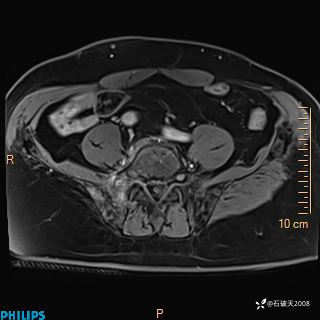

2023年3月份MRI影像

增强轴位